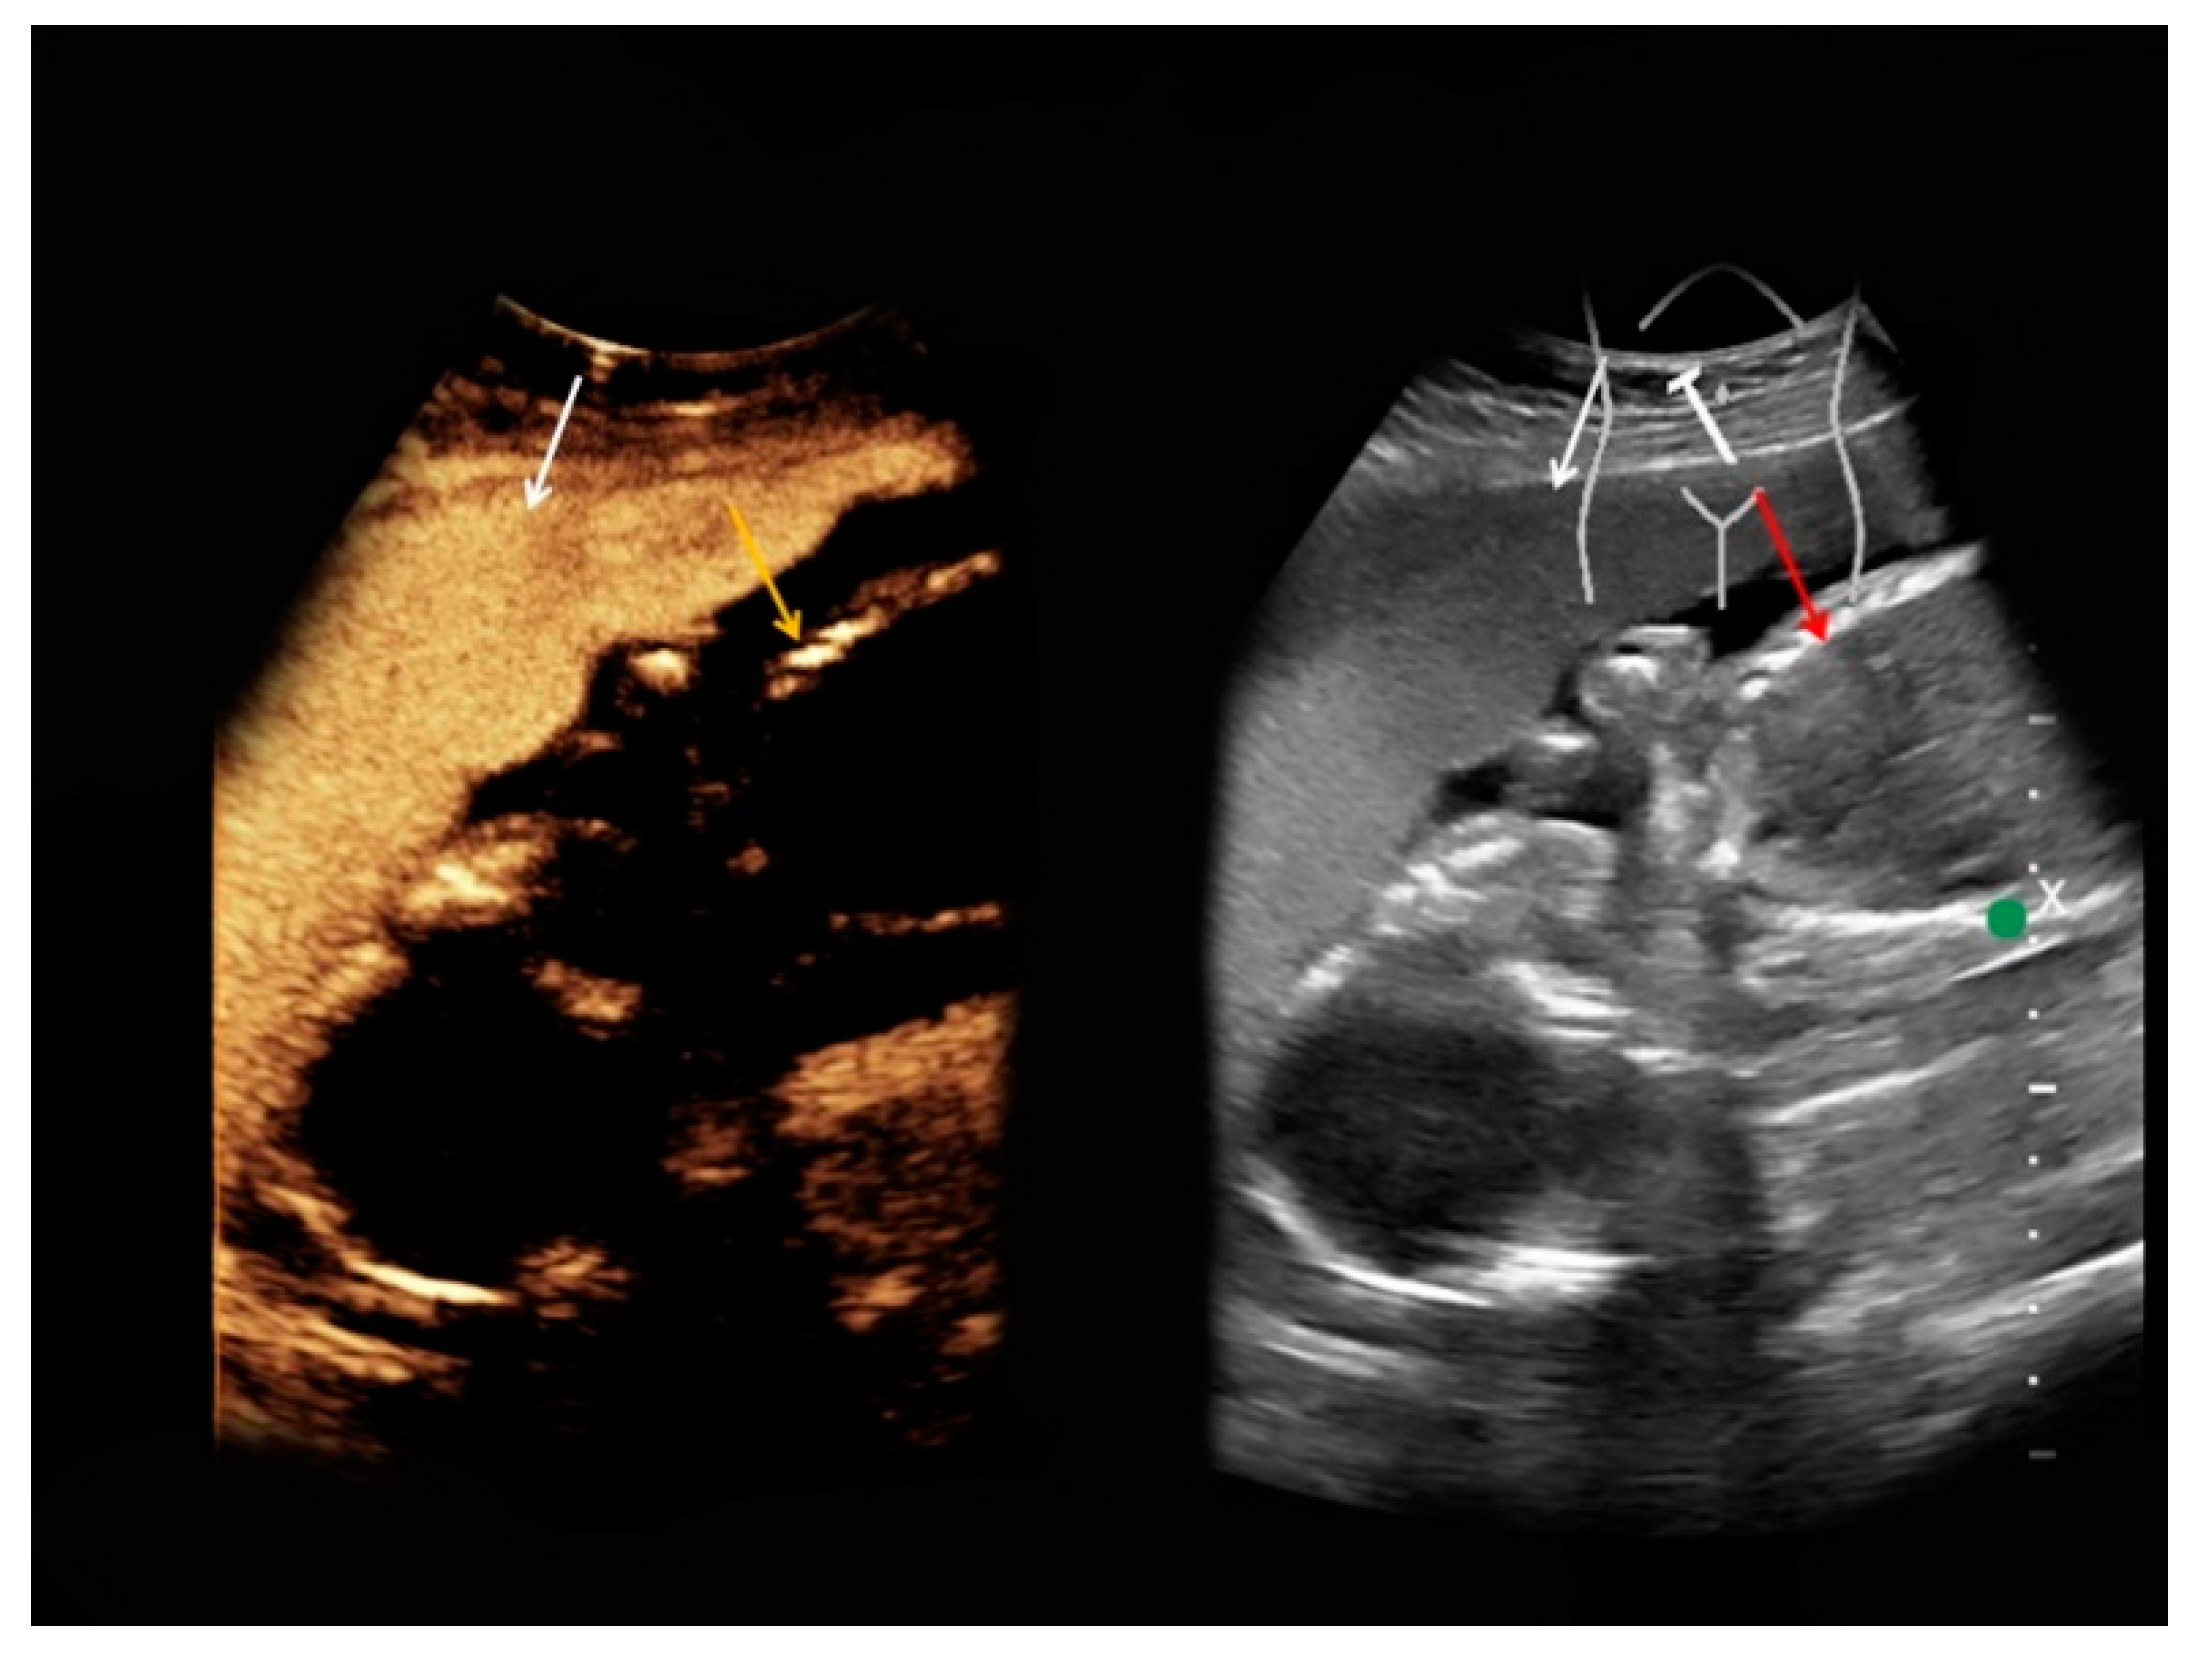

| #5 | 34 | 14 | Superior mesenteric vein thrombosis | B-mode: no abnormalities Doppler: no Doppler signal in the superior mesenteric vein CEUS: only slightly marginal microbubble distribution in the superior mesenteric vein | small superior mesenteric vein thrombosis |